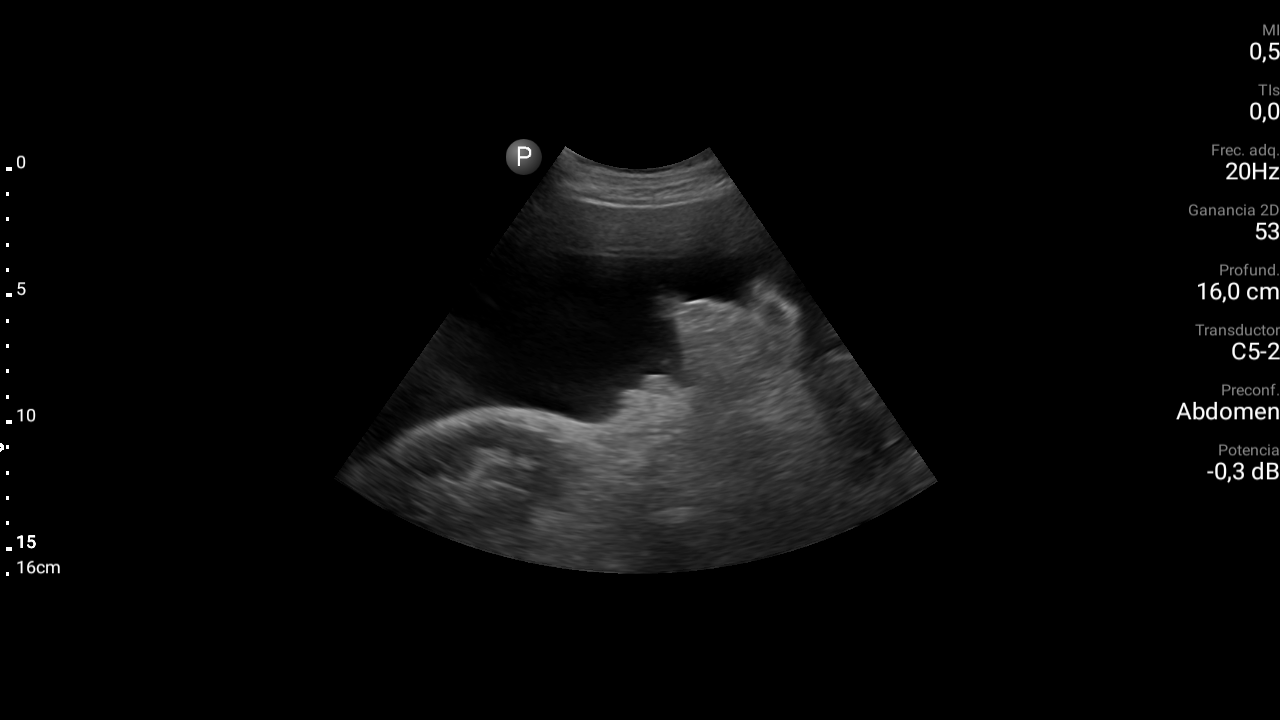

Presencia de ascitis perihepática, periesplénica. En la pelvis se visualizan asas intestinales con aspecto congestivo.

Hígado parcialmente visualizado esteatósico sin lesiones focales.

Derrame pleural bilateral moderado.